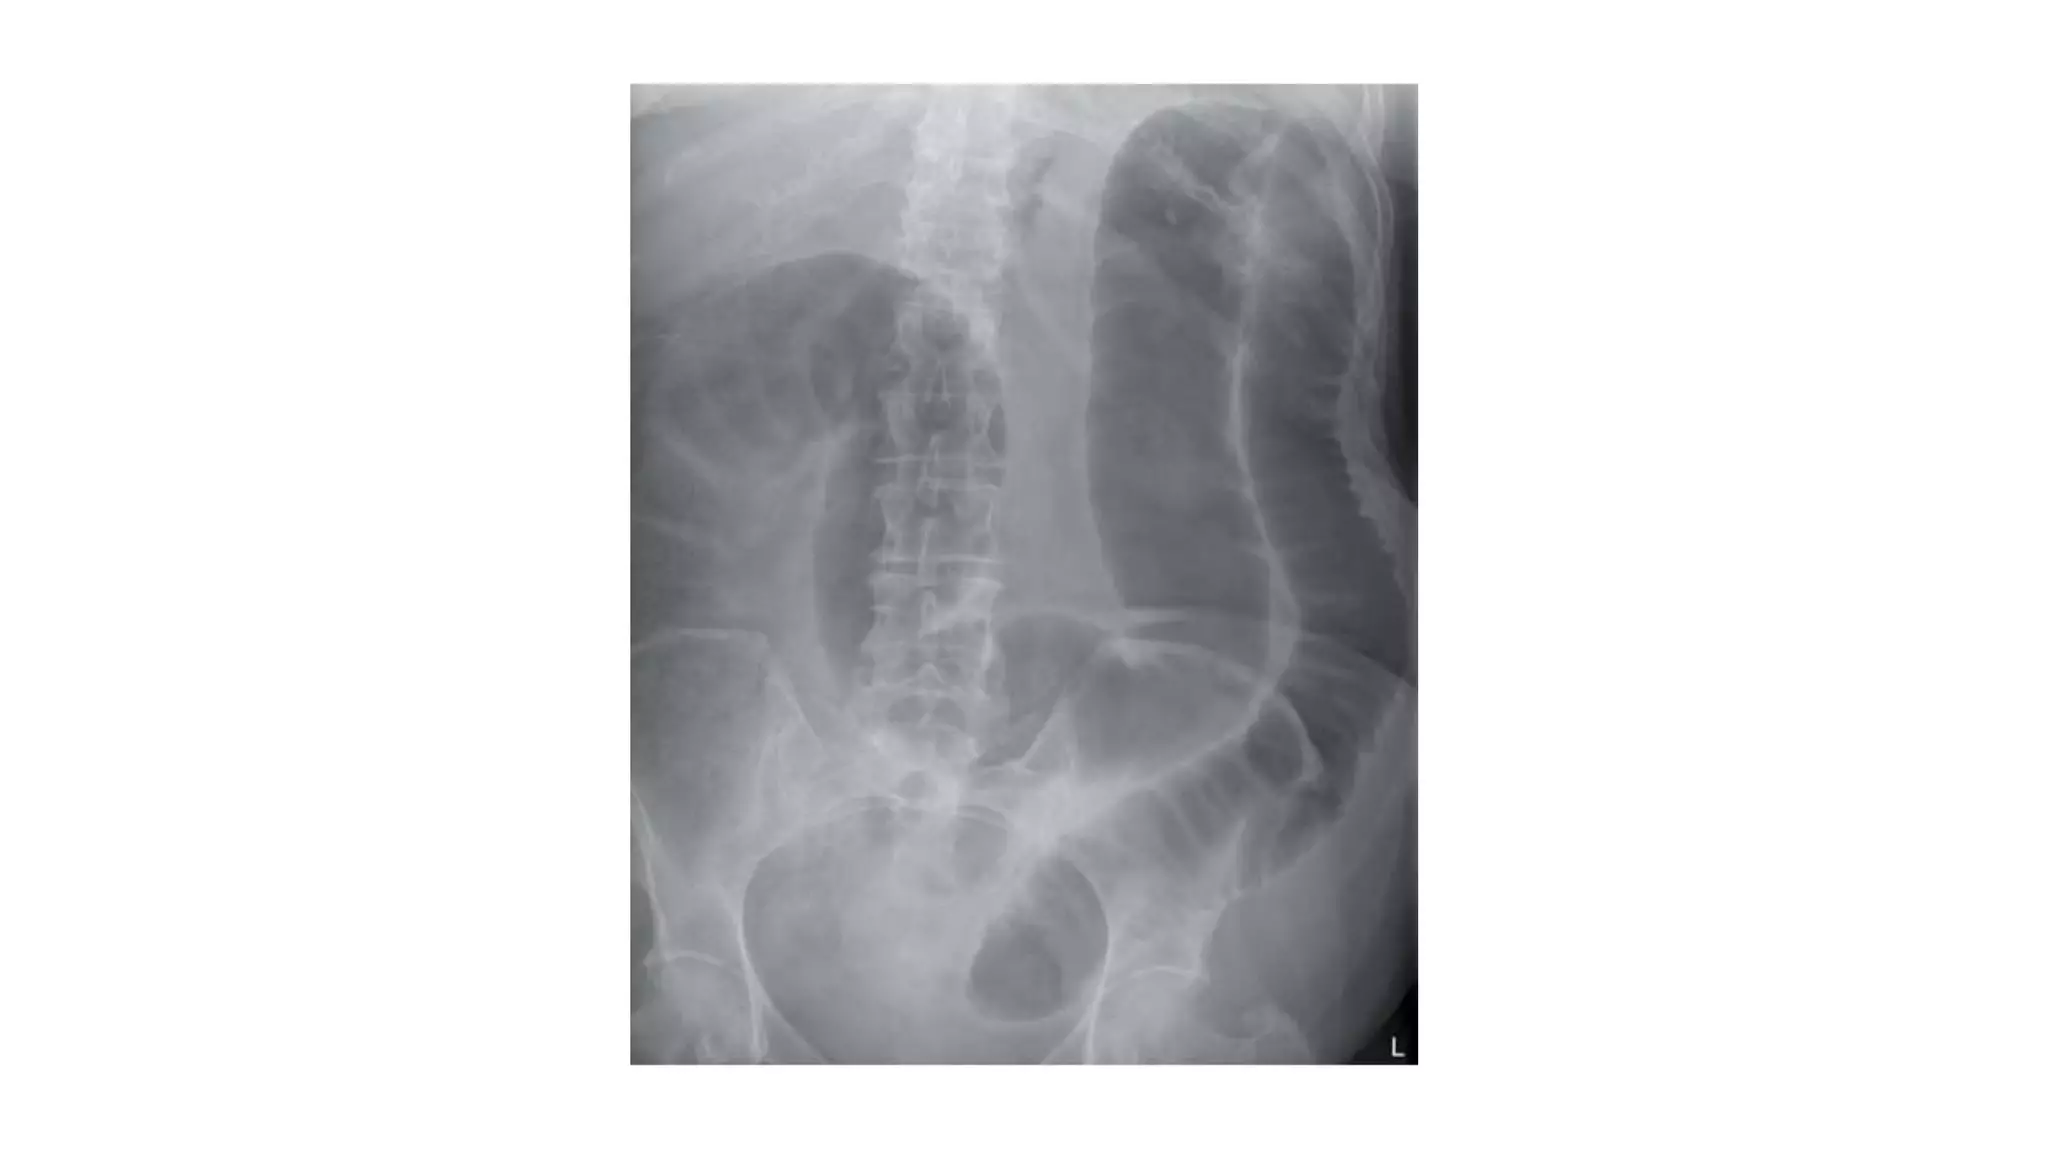

Who wants tobe a hero ?

• 62.

Pick up 3findings

• 65.